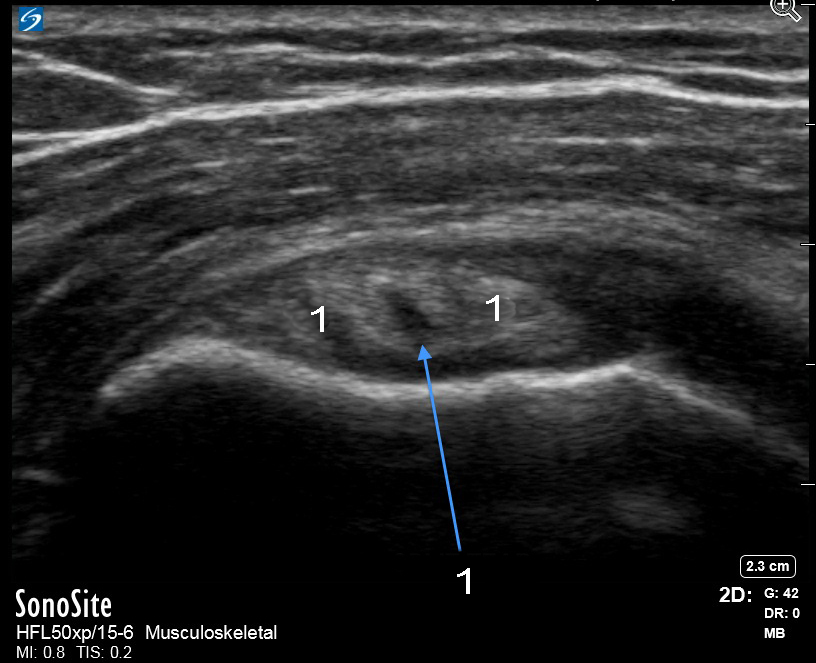

肩ズーム上腕二頭筋腱分割涙画像

分割涙

上腕二頭筋腱(BT)